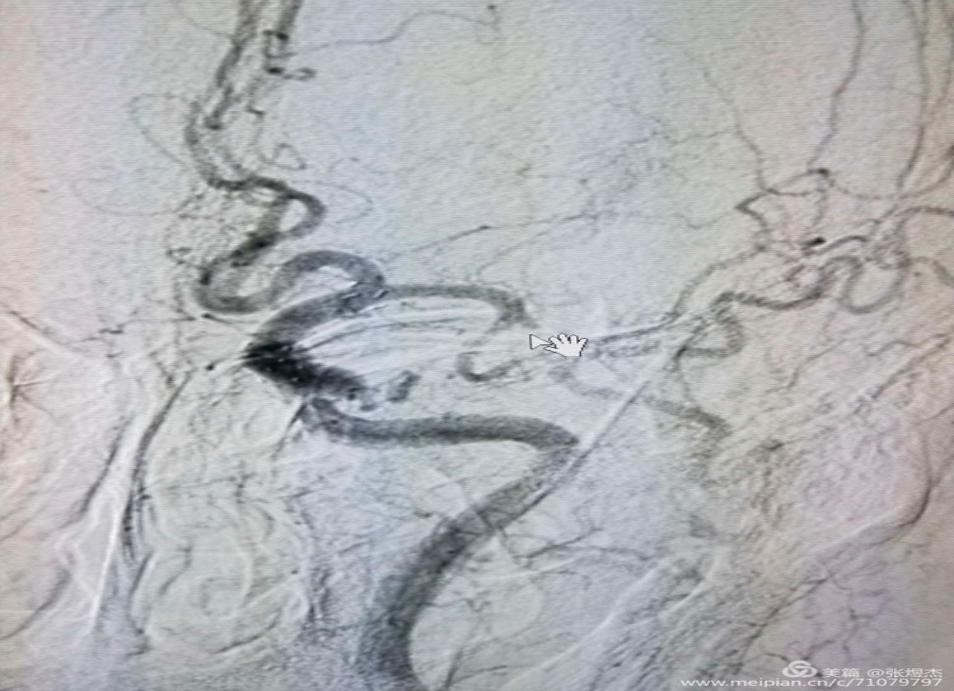

以这个急性脑梗的病人为例,我们先将导引导管放置到颈内动脉起始段,造影显示出左侧大脑中动脉M2上干闭塞,导致左大脑半球皮层广泛缺血,病人情况是突发右侧肢体无力3小时来院。

通过路径图的显示,将微导丝、微导管到达闭塞血管的近端,下一步就需要导丝突破闭塞的血管,这是一处关键步骤,因为闭塞以远的血管血流中断,是没有路径图显示的,图片中蓝色箭头指示的是通畅的下干血管一直向上延续,红色箭头指示的是闭塞的上干血管远端没有显影。